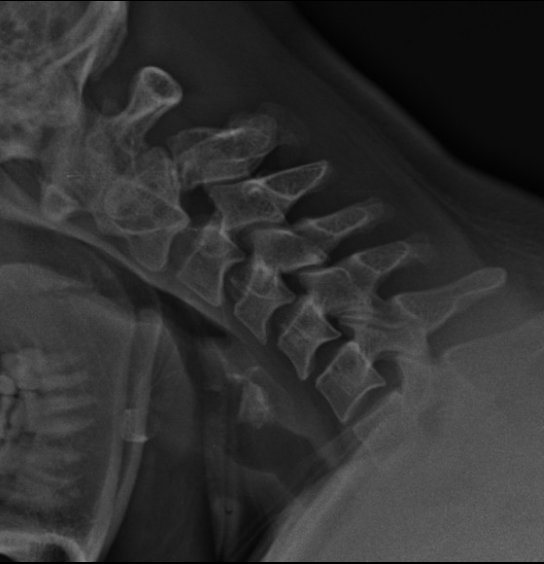

퇴행성 변화(척추증)

- 경추 5-6번 사이 경미하게 좁아진 디스크

- 경추 6-7번 사이 좁아진 디스크와, 갈고리처럼 변형된 골극(spur)

척추분리증

- c-2 뒤쪽 좁은 관절부 결손, 분리